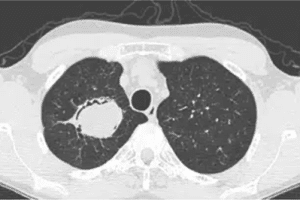

A 65-year-old man visited the physician’s office with a complaint of hemoptysis. He reported having a productive cough with yellowish sputum for the past five days, accompanied by shortness of breath and mild fatigue on exertion. He occasionally witnessed slight streaks of blood in his sputum. He had no fever, chills, night sweats, or weight loss. The patient’s medical history was significant for resolved pulmonary tuberculosis and HIV, which have been under antiretroviral therapy since last year. He had a smoking history of 45 pack-years and consumed alcohol on weekends. On physical examination, mild diffuse wheezing was heard. His vital signs were blood pressure of 136/88 mmHg, a pulse of 102/min, respirations of 18/min, and SpO2 of 91% on room air. Laboratory investigations revealed normal complete blood count results, such as hemoglobin (13.4 g/dL), leukocyte count (10,800/mm3), and normal platelet count (172,000/μL). A chest CT scan was ordered, and the results are shown in the exhibit (Figure 1).

Figure 1: CT Chest

The CT scan revealed several distinctive findings: a solid spherical lesion within the cavity space, an air crescent sign separating a portion or all of the fungal ball from the cavity wall (also observed in conditions like lung abscess, bladder cyst, and granulomatosis with polyangiitis), a Halo sign indicating inflammation surrounding the cavity wall, and a Monod sign, which involves positional changes of the fungal ball relative to the cavity, influenced by patient positioning during imaging. The presence of aspergillus filaments was confirmed by sputum staining.